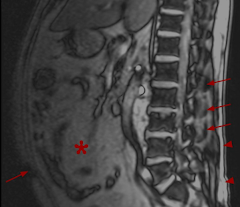

Optimal Imaging for Successful Weight Loss

Optimal Imaging for Successful Weight Loss If you want to lose weight and keep it off for good, visualizing your success can help. Many...